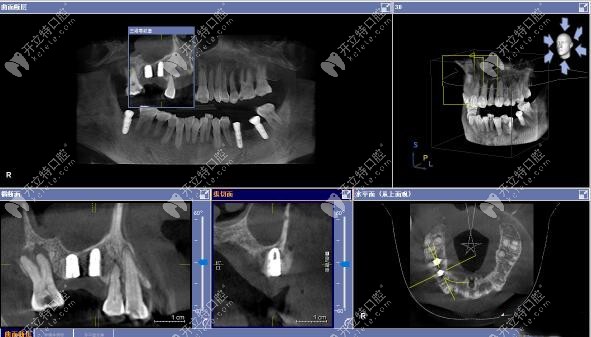

今日分享:用3D數(shù)字化導板技術(shù)做上頜竇區(qū)的精準種植牙案例,植入的是美國皓圣3508和4507型號的種植體。

上頜竇區(qū)種植手術(shù)方案:利用3D數(shù)字化導板技術(shù),上頜15區(qū)缺牙位置種植皓圣3508植體+頰側(cè)GBR、上頜16區(qū)缺牙位置種植皓圣4507植體。

▲術(shù)后CT顯示:上頜15號、16號缺牙位置的植體,均已達到了預期位置。